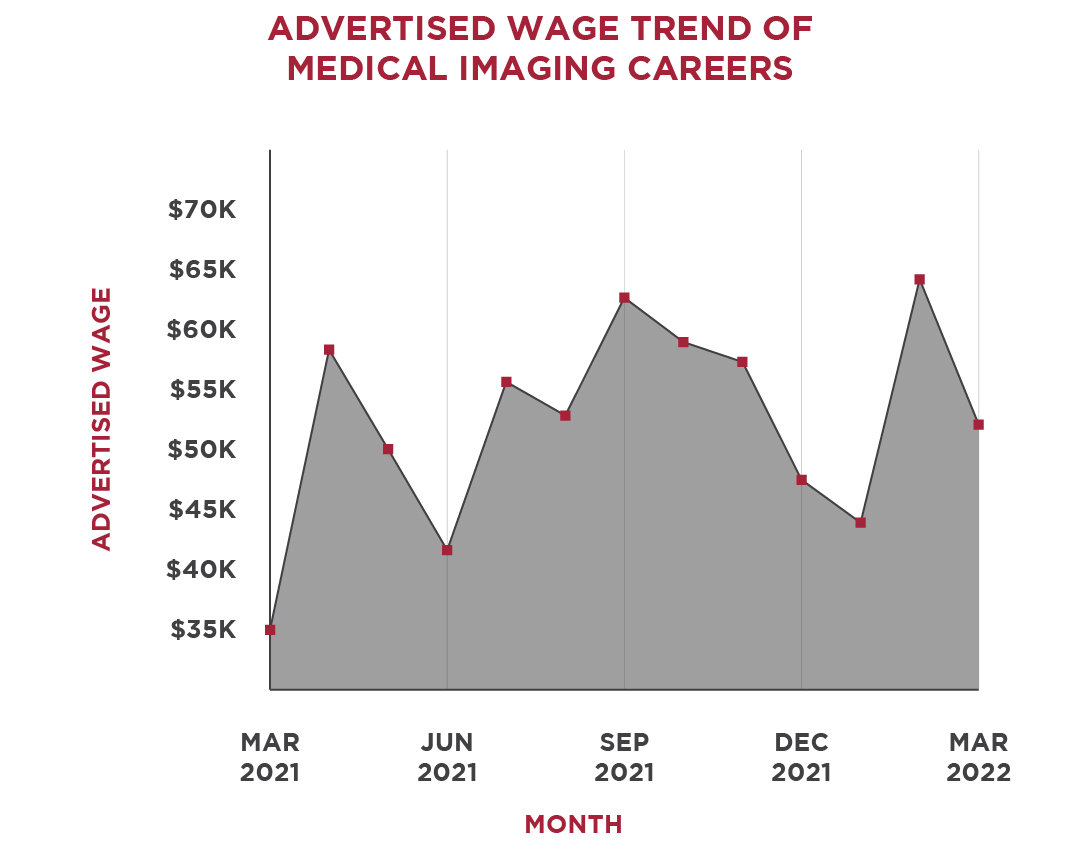

Printable Cute Cats Birthday Card Template For Kids Inkpx free download including neurodiagnostic technologist salaries: what you should know aims the highest paying careers in the medical imaging industry regis college. Careers in neuroscience: what to do with your degree the campus career coach neurodiagnostic technologist salaries: what you should know aims. Jobs salary for a neuroscience major jobs salary for a neuroscience major. The highest paying careers in the medical imaging industry regis college 10 highest paying neuroscience jobs to consider 2022. 10 highest paying neuroscience jobs to consider 2022 10 highest paying neuroscience jobs to consider 2022.

mri tech schools programs salaries jobs salary for a neuroscience major. Neurodiagnostic technologist salaries: what you should know aims mri arrt. Magnetic resonance technologist: occupations in alberta alis day in the life of an mri technologist youtube. L santiago medina pina c sanelli jeffrey g jarvik editors improving the quality of neuroimaging in patient care how can i become an mri tech aims education. Bioinformatics jobs: how to succeed in this competitive space xtalks a high density electroencephalography study reveals abnormal sleep homeostasis in patients with rapid eye movement sleep behavior disorder scientific reports.

pdf improving efficiency in neuroimaging research through application of lean principles noninvasive fluorescence based brain imaging. Comparison shopping: is neuropsychological evaluation more expensive than neuroimaging jobs salary for a neuroscience major. Ariel gilad arielgilad twitter comparing eeg technicians to other neurology careers aims education. List of careers in neuroscience resting state neuroimaging unravels functional organization in the brain. Harmen gudde harmengudde twitter talking brains: 2009.